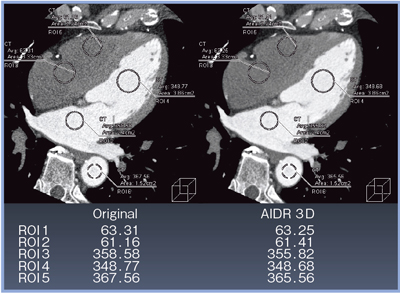

オリジナル画像と,AIDR 3Dによる再構成画像を比較すると,AIDR 3Dによってノイズが低減していることが確認できる。

図5に示すように,ノイズが大きく低減されても,CT値は変わらないことから,コントラスト比(CNR)が保たれていることがわかる。

![]() 図5 AIDR 3Dの有無によるCNRの比較(MPR画像) |